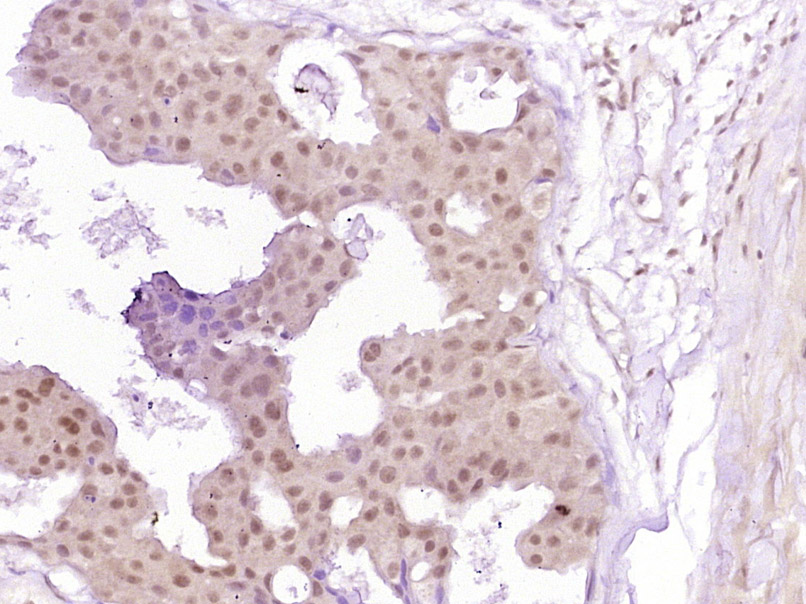

phospho-Smad3 (Ser213) Polyclonal Antibody

Product Name phospho-Smad3 (Ser213) Polyclonal Antibody

IHC-P 1:200-400